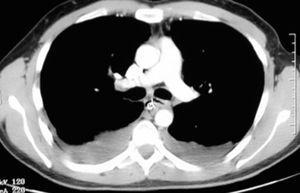

La MND es una entidad poco frecuente, con alrededor de una veintena de casos3,4 descritos en las principales series de la bibliografía. La formación de un absceso en la región bucofaríngea como consecuencia de una infección dental o amigdalar puede desembocar en la formación de una MND. Es un cuadro clínico grave, con una elevada mortalidad incluso actualmente a pesar de los antibióticos de amplio espectro y del desarrollo de la cirugía y de las unidades de cuidados intensivos2,3,6. Su sospecha es fundamental para un diagnóstico temprano, que suele realizarse básicamente mediante la tomografía computarizada8 donde se visualiza la colección líquida, a veces con aire ectópico indicativo de la flora bacteriana anaerobia (fig. 1). La extensión del absceso bucal o cervical hasta el mediastino se comprende puesto que existe una comunicación anatómica a través de los planos de las fascias de los músculos cervicales; además, el mediastino en su parte superior no posee ningún techo cerrado que lo mantenga aislado del cuello. A todo esto hay que añadir la presión intratorácica negativa que facilita, junto con la acción de la gravedad, el descenso de la infección hacia la región mediastínica2. Ante el diagnóstico de una MND hay que actuar inmediatamente con cobertura antibiótica de amplio espectro, ya que suele estar presente una flora mixta polimicrobiana6,11. Actualmente está en discusión el procedimiento quirúrgico en la MND. Algunos autores defienden el drenaje del absceso abordado mediante cervicotomía y toracotomía4,7-9 basándose en la elevada mortalidad de esta afección. Sin embargo, otros autores consideran que un abordaje torácico transcervical10 puede tener un buen resultado, como es el caso que describimos (fig. 2). El mediastino es un compartimiento cerrado, limitado por las pleuras, que lo separan de las cavidades pleurales, pero comunicado cranealmente con la región cervical. Así, el pus procedente del absceso orofaríngeo desciende por el mediastino labrando un camino y permaneciendo estanco siempre que las pleuras mediastínicas no se rompan. Puede haber un derrame pleural reactivo a la mediastinitis (estéril), como en nuestro caso. De este modo es posible el drenaje con facilidad del absceso de una MND mediante la vía transcervical. En el seguimiento hay que atender a la cantidad de líquido drenado y es útil la realización de una tomografía computarizada para una evaluación de control. Progresivamente el tubo torácico se va retirando a medida que cesa el drenaje. A veces conviene realizar lavados con suero fisiológico o con una solución de antiséptico diluido para evitar la obstrucción del tubo. Una vez que los cultivos del drenaje son negativos y que el débito del tubo es escaso, se procede a su retirada. Las radiografías simples de tórax diarias informan de si hay derrame pleural, qué cantidad, si aumenta y, junto con la analítica y la clínica, se podrán realizar otras opciones terapéuticas como la toracotomía con desbridamiento amplio en caso de ser necesario.

Fig. 1. Tomografía computarizada de tórax postoperatoria donde se visualiza el tubo de drenaje torácico colocado en el mediastino posterior vía transcervical.